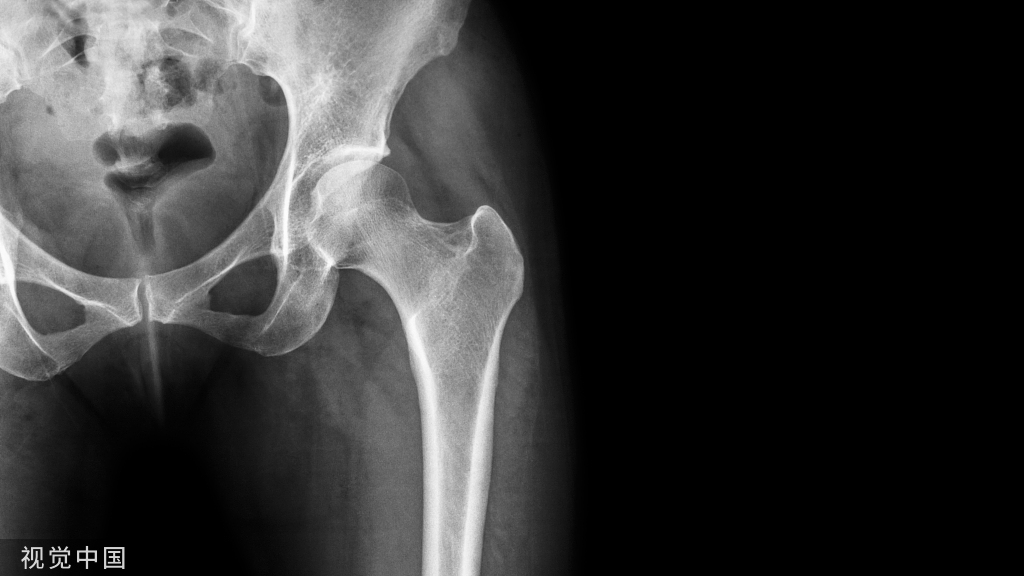

骨折患者创伤后需长期制动,血液高凝状态,同时可能合并血管内皮损伤,极易发生VTE。创伤骨科患者 DVT 发生率为 6. 4%~12. 4%,且以髋周骨折(髋部和骨盆、髋臼骨折)股骨干骨折发生率为最高,合计超过创伤骨科DVT患者的50%,其次为膝关节周围骨折、胫腓骨骨折等。髋周及下肢骨折DVT占创伤骨科DVT患者的95%以上,而上肢骨折DVT发生率很低。